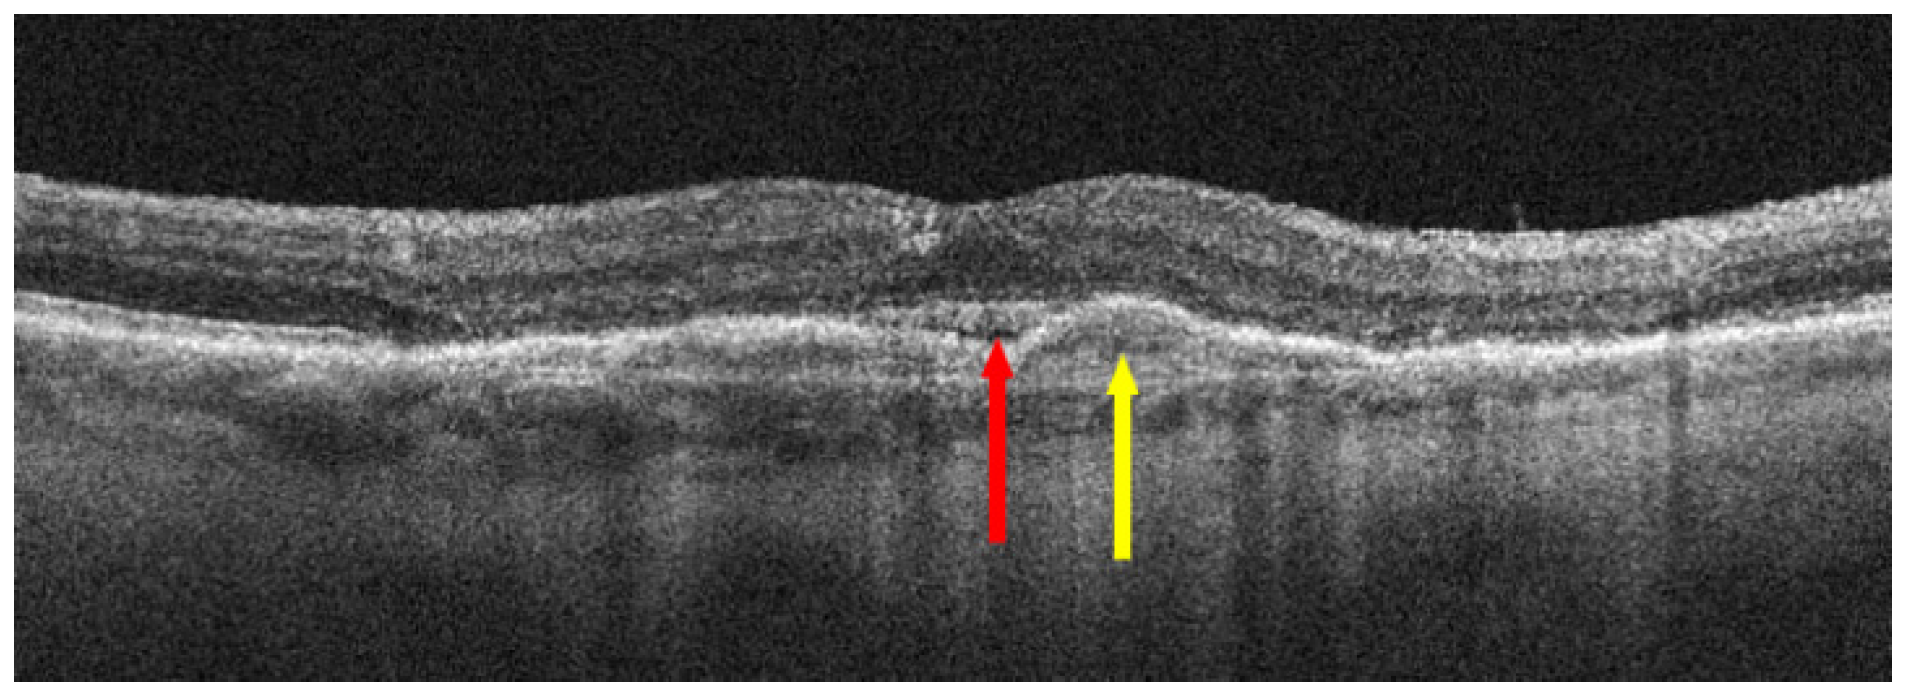

:1. Introduction

3. Treatment of Neovascular AMD